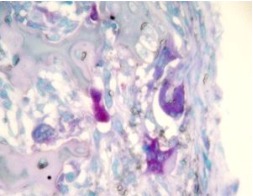

【染色結果】陽(yáng)性反應為鮮紅色或深紅色顆粒,定位胞漿。

①?磷酸酶系列染色液為重氮偶聯(lián)法,染色效果好,磷酸酶的特異性反應沉著(zhù)于胞漿當中,形成紅色或紅棕色的顆粒沉淀。再通過(guò)核染色液的復染色,對比度清晰、分明。